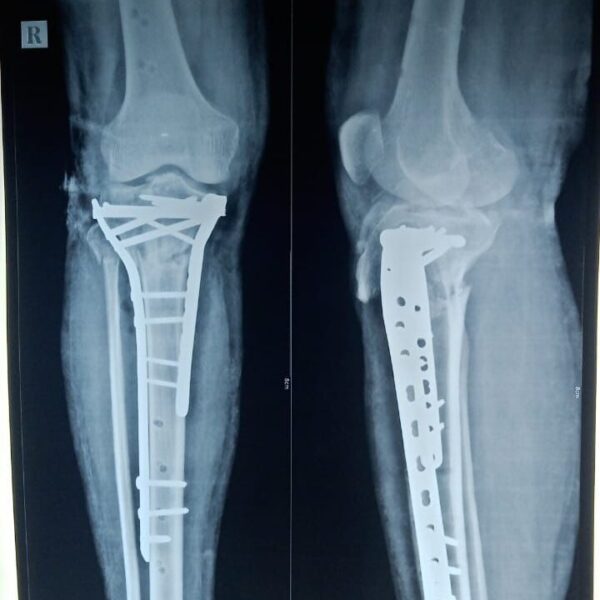

Moments That Mark Meaningful Recovery

Witness real patient transformations at The Ortho Clinic through images that reflect successful treatments and restored mobility.